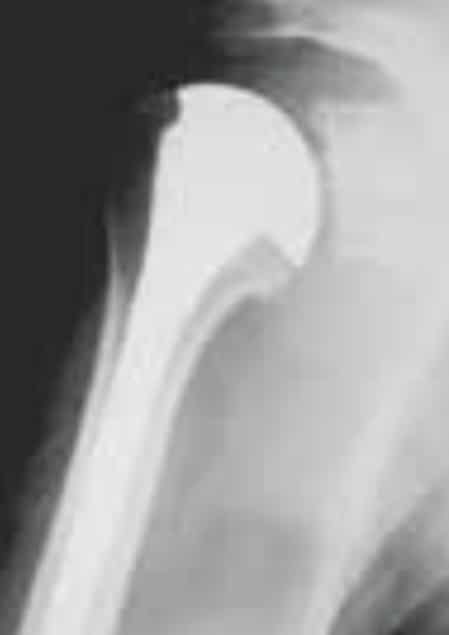

La radiographie de l’épaule met en évidence un pincement de l’interligne articulaire et une production d’os (ostéophytes) autour de la tête de l’humérus, apparaissant comme une goutte.

Prothèse anatomique

Prothèse totale inversée

Quelle prothèse d’épaule, dans quel cas ?

Cette intervention nécessite une courte hospitalisation mais peut, dans certains cas, être réalisée en ambulatoire. Elle permet une indolence et un gain des amplitudes articulaires dans la majeure partie des cas. Aujourd’hui, la longévité d’une prothèse est de 10 à 15 ans, 20 ans pour certains patients.